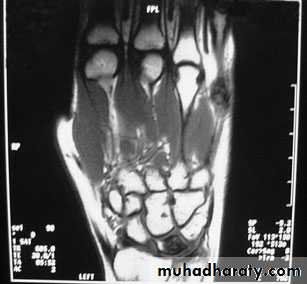

KIENBOCK’S DISEASE

a form of ischaemic necrosis, probably due to chronic stress or injury

Pathology:the pathological changes proceed in four stages

Clinical features:

Imaging:

Radioscintigraphy may reveal

increased activity

X-rays

MRI